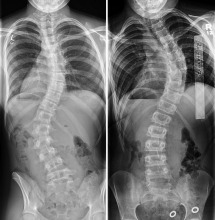

Η Schroth method είναι μέθοδος αντιμετώπισης της σκολίωσης, κύφωσης και της λόρδωσης για ανθρώπους όλων των ηλικιών, είναι επισήμως αναγνωρισμένη από τις διεθνείς επιστημονικές κοινότητες Scoliosis Research Society (SRS) και Society On Scoliosis Orthopaedic and Rehabilitation Treatment (SOSORT), που χρησιμοποιεί ειδικές εξατομικευμένες ασκήσεις προσαρμοσμένες στον τύπο της σκολίωσης.

Βασίζεται στην τρισδιάστατη αυτο-διόρθωση της σκολιωτικής στάσης, στην επιμήκυνση της σπονδυλικής στήλης , στην εφαρμογή της στροφικής αναπνοής και στην εκπαίδευση διατήρησης των διορθώσεων κατά τις καθημερινές δραστηριότητες